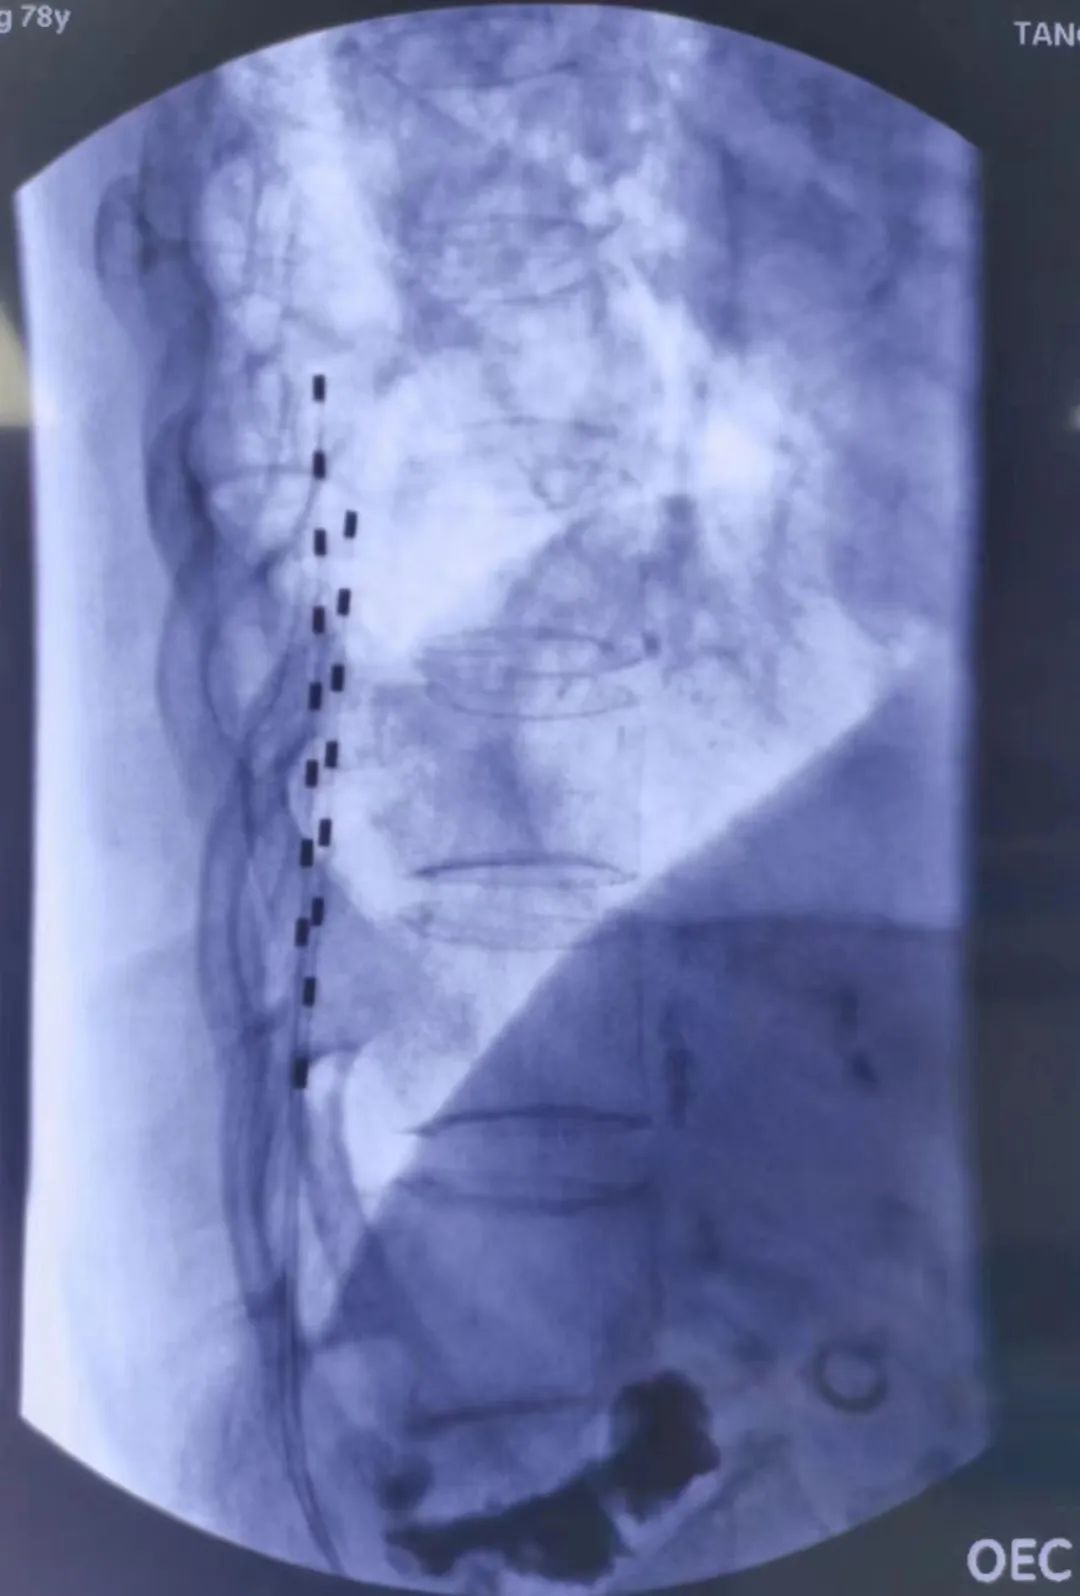

经过细致的检查评估,曹玮主任决定采用目前国际上较为成熟的“脊髓电刺激”疗法来为张阿姨治疗糖尿病足性疼痛,并避免截肢。脊髓电刺激治疗是一种微创疼痛治疗技术,它是在脊髓的硬膜外后间隙插入一根电极,通过电刺激阻断疼痛信号的传导,同时可调控交感神经以改善糖尿病足的末梢血运循环。但是由于张阿姨长期患有类风湿性关节炎,脊柱及四肢严重畸形,无法俯卧位,且椎管多节段狭窄,常规操作无法将电极植入脊椎预定位置,为治疗带来了很大难度。为此,曹玮主任及其团队决定创新采用血管鞘介入技术辅助电极植入,用穿刺针成功引入导丝、导管及血管鞘,通过血管鞘成功建立电极植入通道,之后成功将电极植入至硬膜外脊髓背侧预定的相应刺激区域。在术中测试及术后随访中,张阿姨表示下肢疼痛明显减轻。

经穿刺针置入导丝引导,置入导管及鞘管、引导电极植入